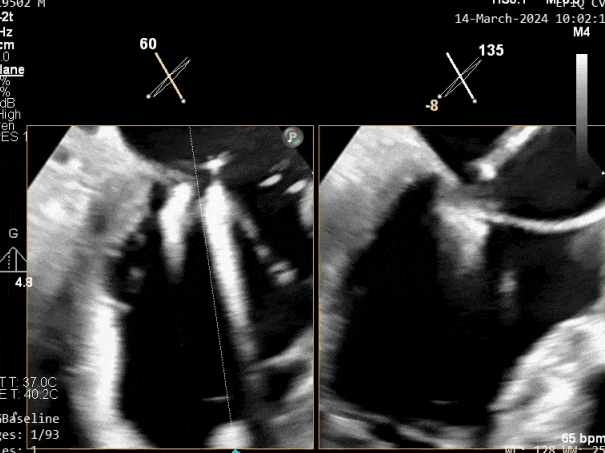

二尖瓣后叶活动受限,呈房源性栓系,以P3区为重,二尖瓣前叶假性脱垂,二尖瓣瓣环前后径49mm,左右径40mm。

PISA法测r=12mm,EROA=0.72cm2,RVOL=100ml,RF 26%。LVEDD 57mm,左房71*59*77mm,右房55*69mm,LVEF 70%。

超声提示:

二尖瓣反流(重度,4+级,Carpentier I型)

2. 本例患者外院超声心动图考虑二尖瓣前叶脱垂,入院后经食道超声心动图明确该患者为二尖瓣后叶活动受限,呈房源性栓系,二尖瓣前叶假性脱垂,超声特征表现为心房功能性二尖瓣反流终末期,呈现出很典型的二尖瓣后瓣环向左室游离壁顶部位移和后叶挛缩表现,同时合并有明显的二尖瓣瓣环扩张、圆形化,左房增大等不利因素,术中通过精准的影像指导和手术操作,成功行TEER,二尖瓣反流程度减轻至微量。